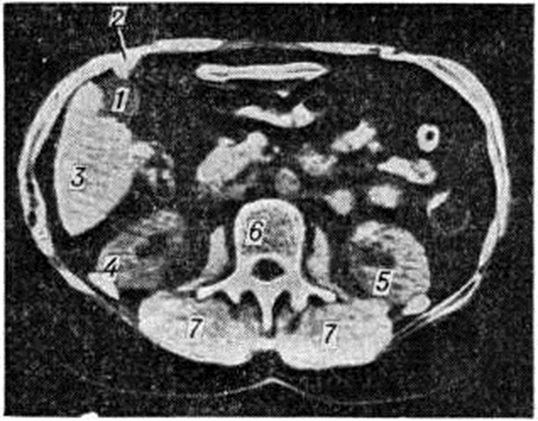

Рис. 6.

Компьютерная томограмма туловища на уровне II поясничного позвонка при некалькулёзном холецистите: 1 — желчный пузырь; 2 — спайка желчного пузыря с брюшной стенкой; 3 — печень; 4 — правая почка; 5 — левая почка; 6 — позвонок; 7 — продольные мышцы спины.

Окончательный диагноз хронический холецистита устанавливают после проведения рентгенологическое и инструментального обследований. Важным методом исследования при хронический холецистите является рентгенологический. Начинать обследование следует с обзорной рентгенографии (смотри полный свод знаний) области правого подреберья, при которой можно обнаружить тени рентгеноконтрастных камней (рисунок 2) или обызвествление стенок желчного пузыря (рисунок 3). После этого производят холецистографию (смотри полный свод знаний) или сочетанную холецистохолангиографию, позволяющие установить наличие в желчном пузыре камней, что проявляется дефектом наполнения (рисунок 4), а также выявить деформацию желчного пузыря (рисунок 5) и нарушение его функции при некалькулёзном холецистите. С помощью ультразвукового исследования определяют состояние стенки пузыря, наличие в нем конкрементов, а также сократительную способность желчного пузыря. Все большее распространение получают метод радиоизотопного исследования желчного пузыря (смотри цветной рисунок 12 и 13), а также компьютерная томография печени, желчного пузыря (рисунок 6) и поджелудочной железы, которые применяются прежде всего у больных с желтухой и у лиц, которым противопоказано (например, в связи с аллергией) обычное рентгенологическое исследование. У больных с желтухой и (или) при непереносимости контрастного вещества (при его внутривенном введении) для уточнения диагноза можно произвести ретроградную холангиографию (смотри полный свод знаний) во время фибродуоденоскопии. Это даёт возможность получить прямое контрастирование желчного пузыря, позволяющее при некалькулёзном холецистите выявить его деформацию (рисунок 7) и нарушение оттока желчи, при калькулёзном холецистите — конкременты в просвете желчного пузыря, а иногда в общем желчном протоке.